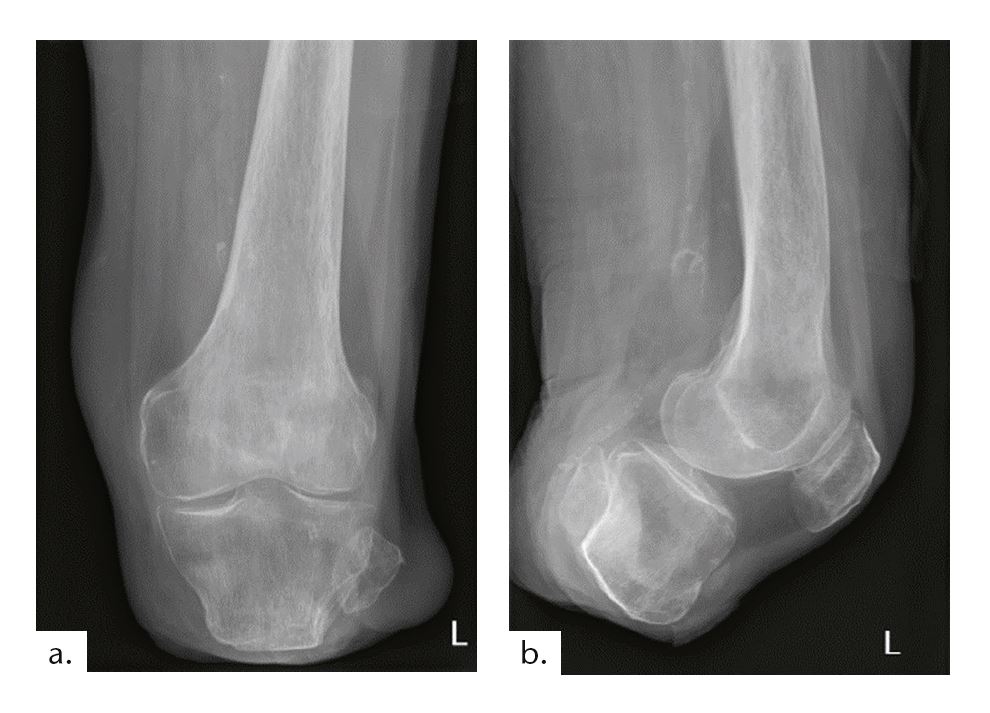

Beim zweiten Fallbeispiel handelt es sich um einen Betroffenen im Alter von 55 Jahren (Mobilitätsgrad 3–4) mit 173 cm Körpergröße bei einem Gewicht von 73 kg. Bei ihm wurde im Alter von 16 Jahren der Unterschenkel aufgrund eines Traumas amputiert. Die Tibialänge beträgt 5,5 cm, die Stumpflänge 6,5 cm mit einer gekürzten Fibula (Abb. 12). Vermutlich aufgrund der Vorversorgungen mit einer PTB-Prothese (PTB = „patellar tendon bearing“) zeigt sich ein Patellahochstand mit daraus resultierender Fehlbelastung und arthrotischer Veränderung. Weil diese Komplikationen als typische Folgen einer PTB-Versorgung anzusehen sind, sollte auf eine solche Versorgung generell verzichtet werden.